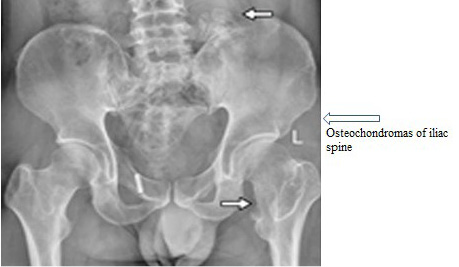

Figure 4

Shows abnormal pelvic with HME